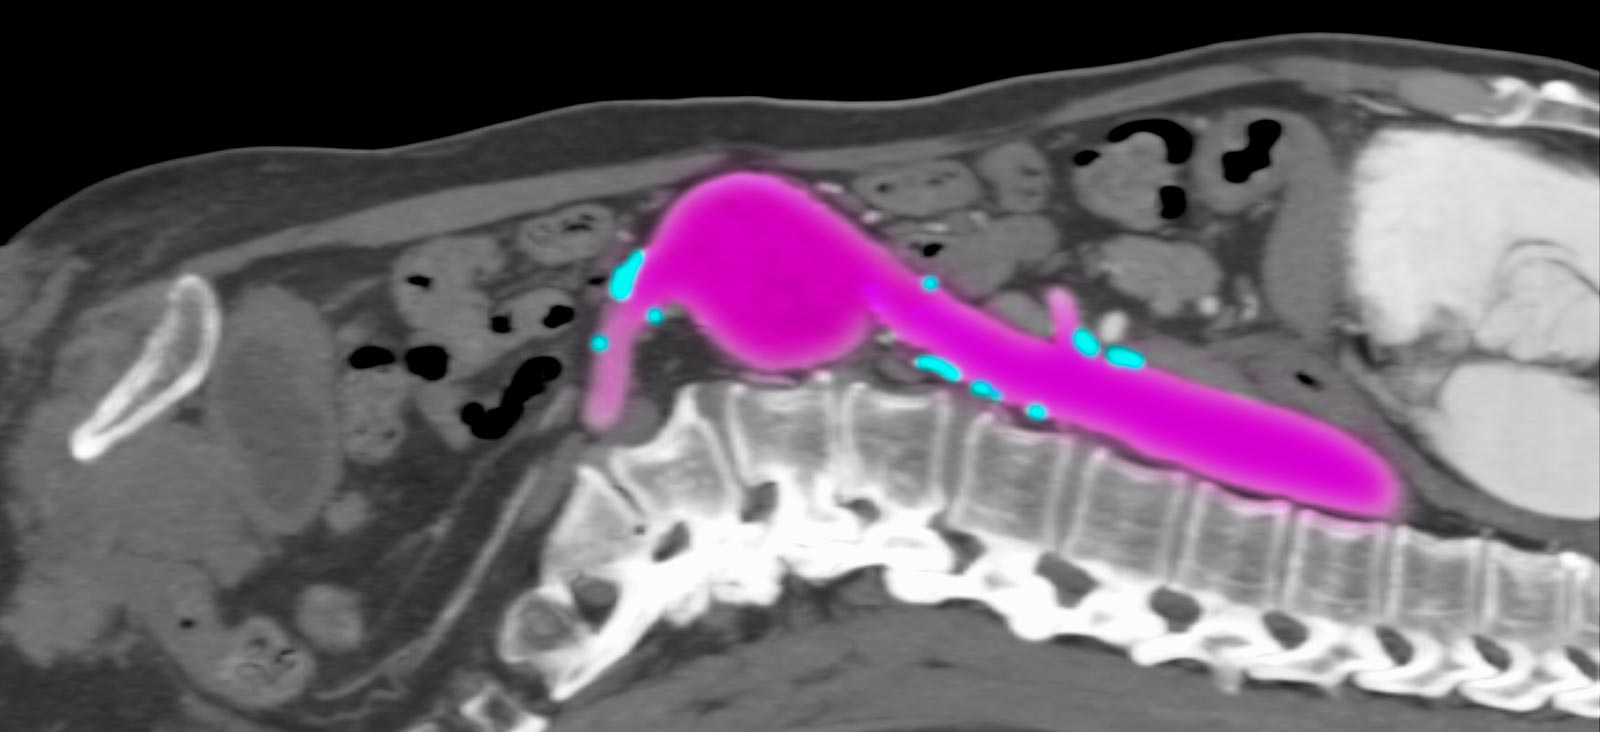

At UT Southwestern, our vascular specialists use computed tomography angiogram (CTA) scans to show detailed images of our patients’ arteries. They use these scans to choose the best treatment approach. Our specialists review patients’ comprehensive medical data to evaluate how an endovascular stent procedure compares with traditional surgical options or determine if a combined approach is needed.

Depending on the patient’s overall health and specific condition, our specialists will recommend the appropriate procedure. UT Southwestern’s Advanced Endovascular Aortic Program focuses on treating complex aortic diseases using total endovascular therapies that are minimally invasive. Led by Carlos Timaran, M.D., the team has developed a Physician-Sponsored Investigational Device Exemption (PS-IDE) protocol, which we have used since 2014 to implant fenestrated and/or branched stent-grafts.

With these devices, our vascular surgeons can repair most aortic diseases, such as complex suprarenal (above the kidneys) and thoracoabdominal aortic aneurysms and chronic dissections, using this minimally invasive approach. Our endovascular aortic approach is appropriate for most patients, even those who cannot have open surgery, providing a faster recovery.

If patients are eligible for an endovascular stent procedure that allows a more rapid recovery, the surgeon will use live radiological images during the procedure to guide a catheter through a blood vessel to the location of an aneurysm to deploy the endograft for repair.